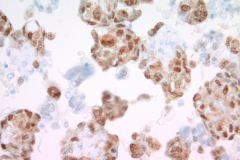

Immunohistochemistry (IHC) stains can also be an important tool in proper diagnosis of EHE. Stains such as CD31, CD34, and ERG have been described to stain EHE.2,3 CD31 is a platelet endothelial cell marker expressed frequently in vascular endothelial cells. CD34 stains for 90% of vascular tumors because it is a highly glycosylated transmembrane glycoprotein associated with the origin of vascular tumors. Positive staining for both CD31 and CD34 is considered diagnostic of this tumor.1 In this case, we have CAMTA1, a tumor suppressor transcription factor, staining positively for EHE shown in Image 1.

Epithelioid Angiosarcomas are very rare soft-tissue sarcomas that normally appear in the skin, liver, and breast. Cytologically, they can take on a wide range of features. The endothelial cells of these tumors can be bland or pleomorphic. They can have a single-cell pattern in high-grade tumors with spindle-shaped to oval nuclei or can present in papillary groups with whorls or rosette-like groups important for diagnosis. Similar to EHE, the nuclei of low-grade tumors can have nuclear grooves, fine chromatin, and be slightly pleomorphic. High-grade tumors can also present with abundant cytoplasm, prominent nucleoli, and binucleation. Unlike EHE, epithelioid angiosarcomas can have hyperchromasia, large cell varieties, and can display erythrophagocytosis. DeMay describes this phenomenon as “an attempt at neovascularization.”5 IHCs that can help differentiate the two tumors include vimentin and cytokeratin markers AE1/AE3 for epithelioid angiosarcoma due to its epithelial origin.8 CAMTA1 can also be used to confirm epithelioid hemangioendothelioma over epithelioid angiosarcoma.2